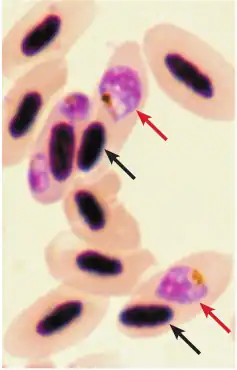

Cellules sanguines d'un 'apapane infecté par Plasmodium relictum (flèches rouges).